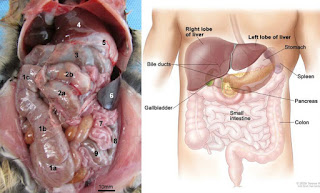

There are eight endocrine glands in a human body. The adrenal glands (2 of them), the parathyroid glands (4), the thyroid gland (1), the pineal gland, the pancreas, the ovaries (2) or testes (2), the hypothalamus, and the pituitary gland. They can be stimulated to release hormones by either neurons, other hormones, or other chemicals. Besides these well known glands, a few tissues will release hormones in specific situations. The placenta will release progesterone and estrogen, and the stomach can release gastrin to stimulate gastric juice (acid) and ghrelin to stimulate hunger.

In addition to endocrine glands, there are also some cells that can be directly stimulated by neurons to release hormones into the blood. These are the neuroendocrine cells. There’s a lot more of them you think, and they’re just about everywhere in your body.

For one example, there are pulmonary neuroendocrine cells (PNEC) in every part of your respiratory tract, from your nose to your alveoli. While they seem to act like neurons in many respects, they are derived from epithelial tissue, not the neural crest tissue that all neurons come from.